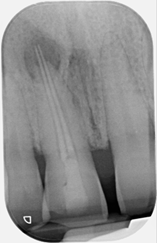

Root canal retreatment and bypass of separated instrument

Pre-op

12 month review demonstrating healing